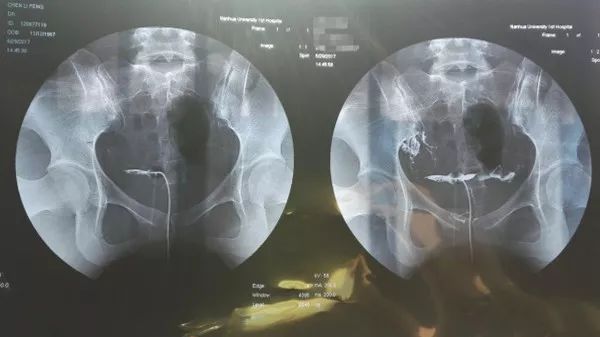

输卵管通畅

造影片可以看到一侧或双侧输卵管伞端有造影剂溢出,盆腔有造影剂涂抹。术后积极试孕,这一般没有争议。

输卵管梗阻

造影片显示一侧或双侧输卵管不显影或部分显影,盆腔没有造影剂涂抹。如果盆腔有造影剂涂抹,说明至少一侧输卵管是通的。如果一侧输卵管通也是可以试孕的。如果双侧不通,可考虑做腹腔镜或试管婴儿。